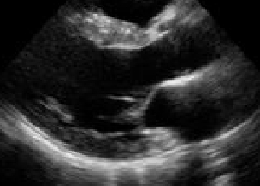

- さらに、血圧により心臓や他の臓器に障害が引き起こされていないかを確認するために、胸部レントゲン検査、心電図、血液検査、心臓超音波検査(心エコー図検査)、24時間心電図検査、頸動脈エコー検査等が必要になります。

Hypertensive Hypertrophic Cardiomyopathy

- 高血圧症により引き起こされた心疾患。

- 心エコー図法では、高血圧性心疾患で注意が必要な所見の計測、分析を行います。

- また、心機能分類を行います。